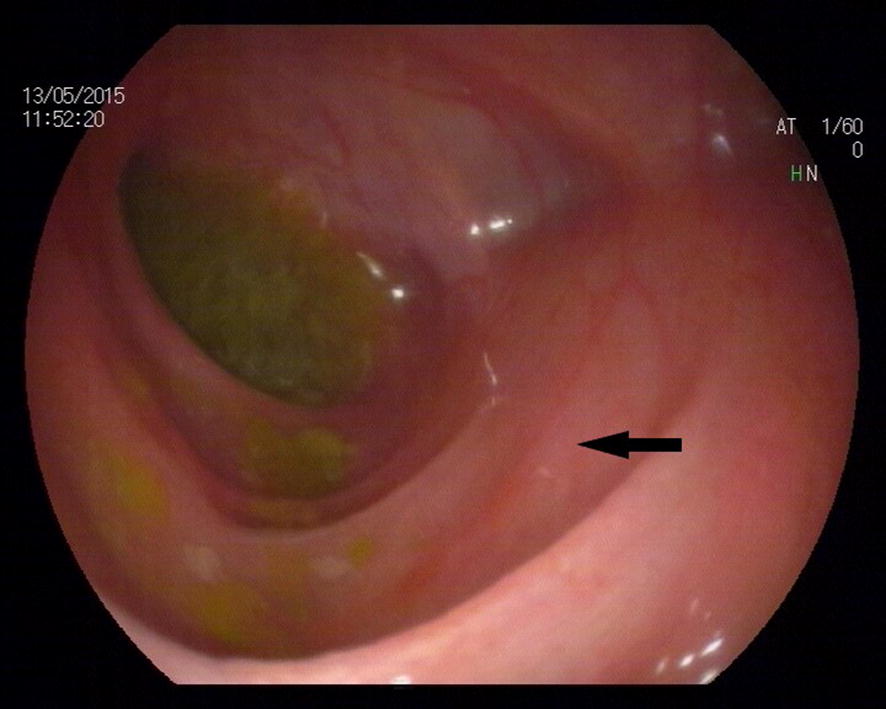

After the infant started receiving feeding, he suffered from a relapsing infection. WBC count and CRP level increased to 28.9 × 109/l and 156 mg/l, respectively. The temperature, WBC, and CRP returned to an acceptable range as vancomycin and meropenem (20 mg/kg, Q8 h) were given. A colonoscopy was performed on the infant, which indicated the smooth intestinal mucosa and clear intestinal wall vessels (Fig. 1). A distal stoma imaging was also performed on the infant, which revealed a rigid lumen from the transverse colon to the descending colon (Fig. 2).

Fig. 1.

Colonoscopy graphic (transverse colon). The black arrow shows a smooth intestinal wall and clear vessels